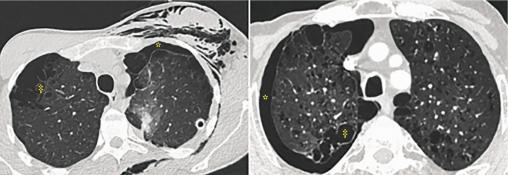

Pneumothorax spontané (*) et emphysème (‡). Figure à gauche, patient de 29 ans, 12 PA, 42 JA. à droite, patient de 65 ans, 100 PA.